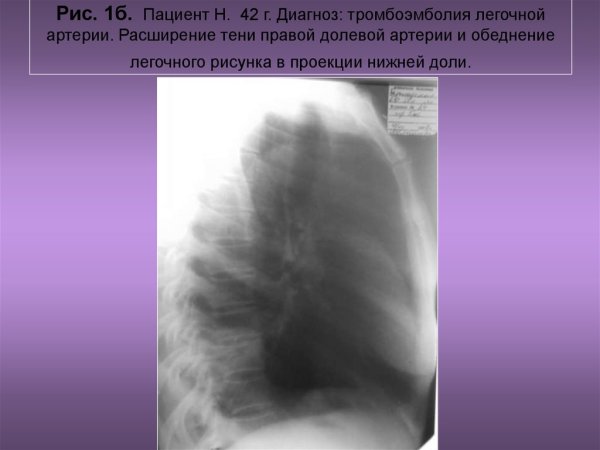

Тромбоэмболия легочной артерии рентген